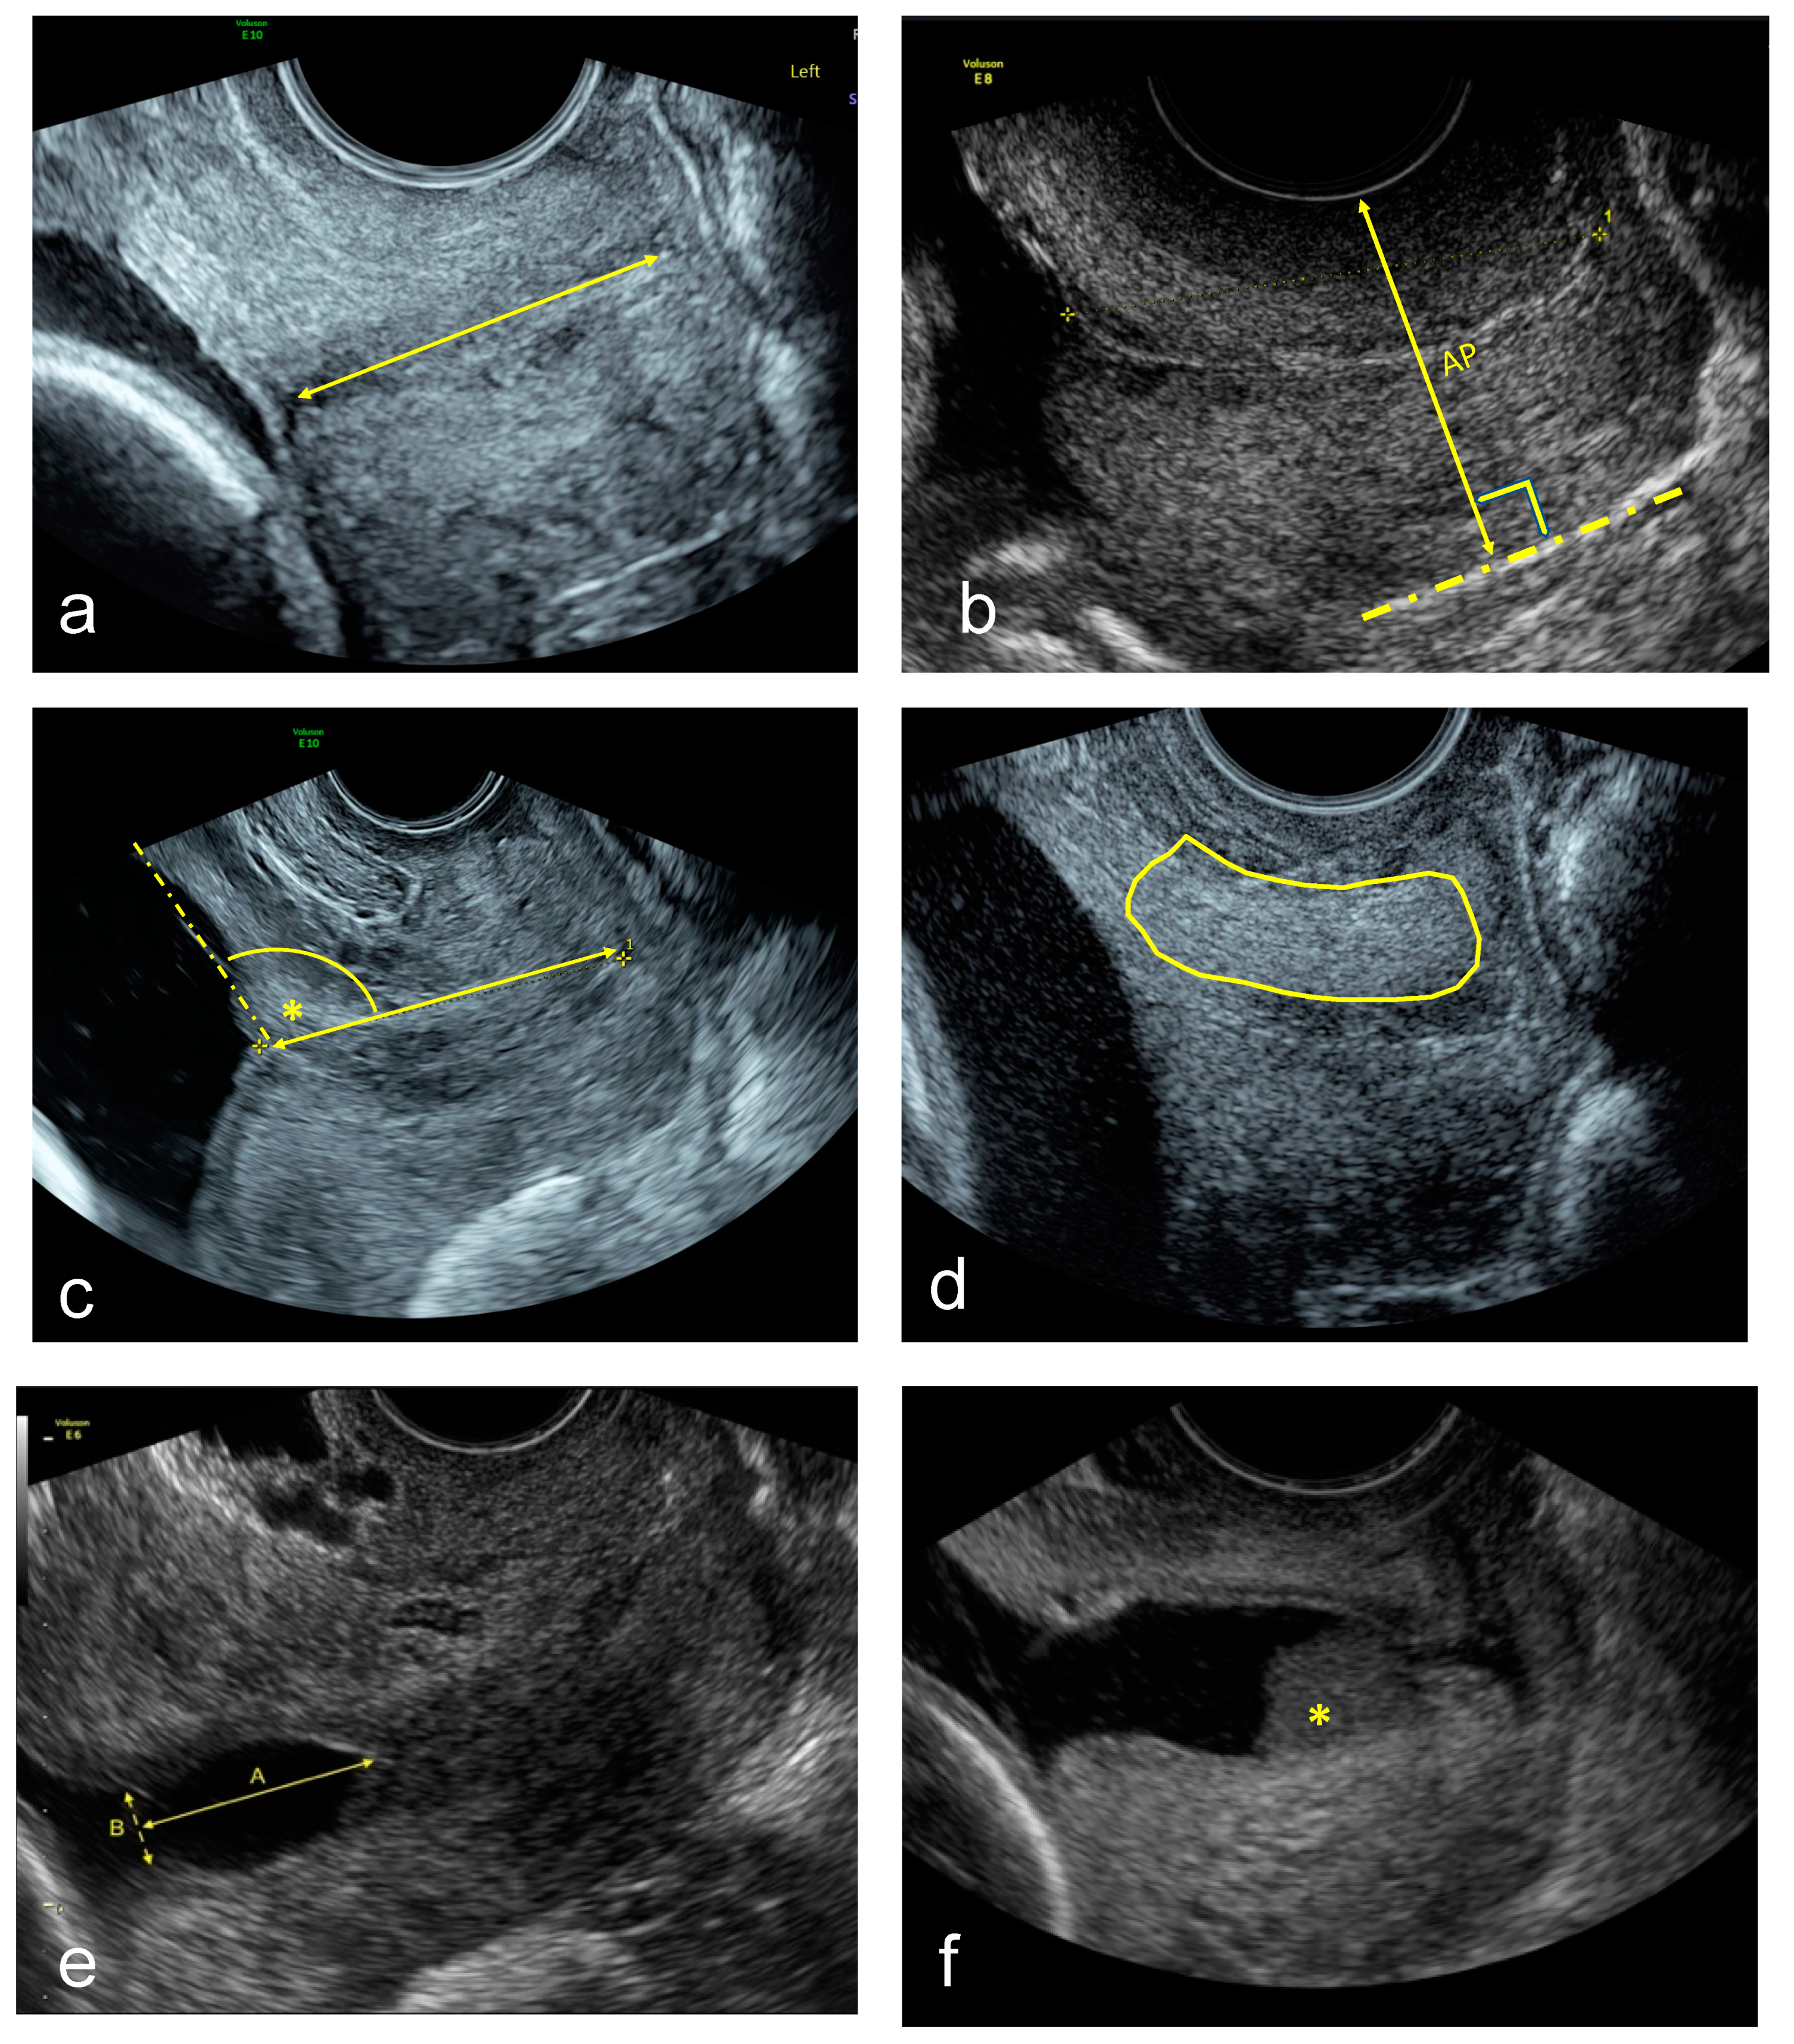

For TVU image acquisition, a Voluson E8 or E10 (GE Medical Systems, Zipf, Austria) equipped with a vaginal probe with a frequency of 2–10 MHz was used. A set of images was acquired with the woman in lithotomy position after emptying her bladder. Firstly, a sagittal view of the cervix without exerting any pressure with the transducer was obtained, as described previously [21], upon which the cervical canal and the internal and external cervical os were clearly seen. This image was used for the CL and UCA measurement, and to assess for funnelling or sludge presence. A second image was then saved without any speckle reduction imaging or cross beam imaging post-processing to do the CTx analysis. Additionally, a video clip in which pressure was applied softly and progressively on the cervix until no further compression of the anteroposterior diameter could be observed. The technique used to apply the maximum compression was done as described by Parra-Saavedra et al. [11]. The images were downloaded from the medical imaging software and stored in a research imaging server for off-line analysis. Quality criteria to consider an image were: (1) the entire cervix seen and (2) the cervical canal not inclined more than 45° over the horizontal plane. All measurements were done blinded to the pregnancy outcome and measurement methods are depicted in Figure 1:

• Standard CL (straight-line) measurement in mm [21].

• CCI measurement expressed as a percentage [11]. A straight cervical length was traced to align with the longitudinal axis of the cervix at the posterior vaginal wall. Then the midpoint of this line was calculated, and the anteroposterior diameter was measured perpendicular to this line with (AP’) and without (AP) pressure. Then the cervical consistency index was calculated with the following formula:

CCI = (AP′/AP) × 100

• UCA calculated by measuring the angle between the straight anterior myometrial wall line and cervical length tracing [15].

• CTx was done as described using a machine learning algorithm [18].

• TVU cervical funnel analysis with and without fundal pressure and defined as protrusion of the amniotic membranes into the cervical canal. The longest and widest funnel length were taken at the internal os [21].

• TVU amniotic fluid sludge presence defined by the presence of hyperechogenic free floating particulate matter, in the proximity of the internal cervical os [21,22].

Figure 1. Example images of (a) Transvaginal ultrasound cervical length (straight-line) in mm. (b) Cervical consistency index measured as the ratio of the anteroposterior diameter with and without pressure and expressed as a percentage, CCI = (AP′/AP) × 100. (c) Utero-cervical angle calculated in degrees. (d) Cervical texture analysis. (e) Cervical funnel analysis, the longest and widest funnel at the internal os in mm. (f) Presence of amniotic fluid sludge (*).